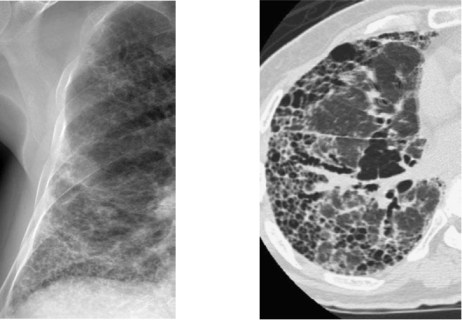

– Caso. Patrón en panal: Opacidades pulmonares subpleurales con imágenes aéreas quísticas menores de 1cm en su interior con un aspecto reticular. Suele acompañarse de pérdida de volumen por patología restictiva. La presencia de panalización puede significar lesión destructiva final con fibrosis y distorsión de la arquitectura pulmonar de grado severo.

Causas:

- Enfermedades del Tejido conectivo (esclerodermia, artritis reumatoide, dematopolimiositis, polimiositis).

- Fibrosis pulomnar idiopática, Neumonía intersticial usual.

- Histiocitosis X.

- Neumoconiosis.

- Sarcoidosis.